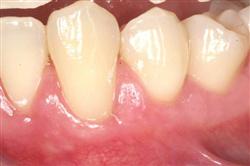

In addition to the functional problems previously mentioned, receding gums can look unsightly.

Longer looking teeth and exposed tooth roots give an "old" appearance to your smile. Some people cover their mouths when they smile for this very reason.

Cosmetic Soft Tissue Grafting can add a new youthful appearance to your smile. In your initial consultation with Dr. Hoidal, he will thoroughly explain what can be achieved in your particular case.